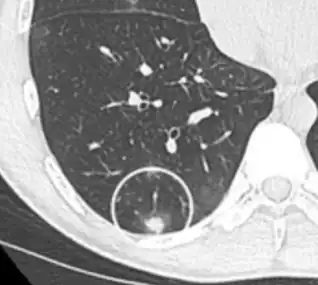

Nodular

There are numerous potential causes of nodular GGOs which can be broadly separated into benign and malignant conditions. Benign conditions potentially leading to the formation of nodular GGOs include aspergillosis, acute eosinophilic pneumonia, focal interstitial fibrosis, granulomatosis with polyangiitis, IgA vasculitis, organizing pneumonia, pulmonary contusion, pulmonary cryptococcus, and thoracic endometriosis. Focal interstitial fibrosis presents a unique challenge when differentiating from malignant nodular GGOs on CT imaging. It is typically persistent over long-term imaging follow-up and shares a similar appearance to malignant nodular GGOs.[9]

Pre-malignant or malignant causes of nodular GGOs include adenocarcinoma, adenocarcinoma in situ, and atypical adenomatous hyperplasia (AAH). One large review study found that 80% of nodular GGOs which were present on repeated CT imaging represented either pre-malignant or malignant growths. Differentiating between pre-malignancy and malignancy on the basis of CT alone can pose a challenge to radiologists; however, there are several features that are indicative of pre-malignant nodules. AAH is a pre-malignant cause of nodular GGO and is more commonly associated with lower attenuation on CT and smaller nodule size (<10 mm) compared to adenocarcinoma.[10] In addition, AAH often lacks the solid features and spiculated appearance that are often associated with malignant growths.[9] In contrast, as adenocarcinoma becomes invasive it will more often cause retraction of adjacent pleura and may show an increase in vascular markings. Nodules >15 mm almost always represent an invasive adenocarcinoma.[9][10]

- CT image showing ground-glass nodule (circled).